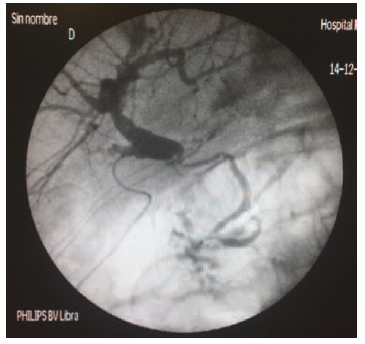

The patient required surgical revision. Intraoperatively scarce bile was observed in the Morrison space, with intact biliary anastomosis and correctly placed T tube. Cholangiography was performed, as usual, injecting contrast through the Kehr catheter. This allowed contrast leak to be observed through the graft’s cystic duct stump on cholangiography. After that, surgical revision was carried out. Serum saline was injected trans-Kehr during the surgical intervention to verify the cholangiography findings and to identify the origin of the leak. Primary suture of the defect was performed (Figure 1). An intraoperative cholangiography showed no other points of leakage and showed contrast passage into the native common bile duct and duodenum, using augmented pressure due to bile duct diameter discrepancy (Figure 2). Previous failure of endoscopic management and the reduced diameter of the native bile duct resulted in need for biliary bypass surgery with Roux-en-Y hepaticojejunostomy.

Figure 2. Intraoperative Cholangiography of Patient